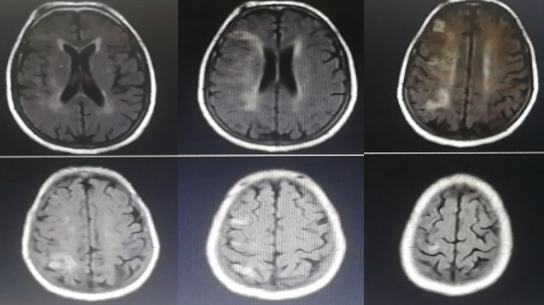

入院影像检查

头部CT:

未见脑出血征象,右侧基底节区、顶叶、侧脑室体旁多发点片状低密度阴影。

头部CTA:

右侧大脑中动脉M1段闭塞,M2-M5血管部显影。

头颅MRI:

未见脑出血征象,右侧基底节区、侧脑室体旁多发点片状异常信号影。

头颅MRA:

右侧大脑中动脉显影差。

CTP:

右侧大脑半球均存在不同程度的低灌注区域。